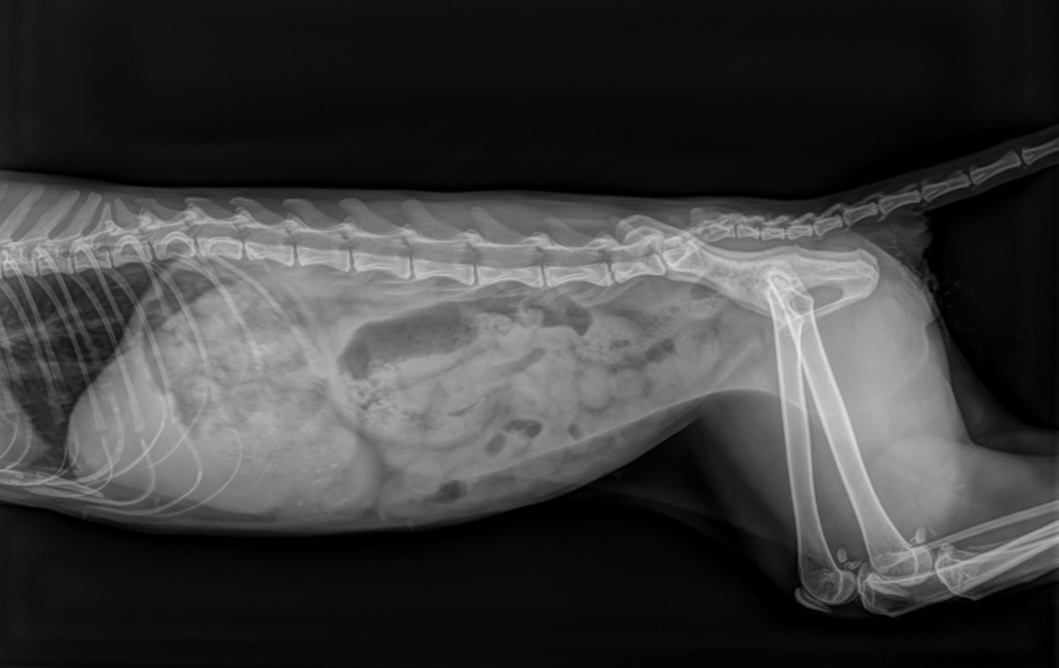

Als man mich fand, war ich sehr krank. Ich hatte Pyometra, meine Gebärmutter war lebensgefährlich entzündet. Aber das habe ich überlebt, nur leider ist das nicht alles.

Mein Schwanz war bereits gebrochen. Die Tierärzt:innen sagen, die Verletzung stammt wahrscheinlich durch Schlagen, Treten oder einem dumpfen, heftigen Aufprall. Was genau passiert ist, weiß ich nicht mehr. Ich weiß nur, dass dabei etwas in mir kaputt gegangen ist.

Anfangs war ich inkontinent, aber Zoryana, meine Pflegemama von damals, sagt, es hatte sich gelegt. Mein Schwanz hängt heute einfach runter. Er funktioniert nicht mehr wirklich. Ich komme damit aber gut zurecht. Wirklich! Ich laufe, spiele und kuschle so gern!

Nur ist seit kurzem die Inkontinenz wieder da und ich verliere Kot. Und genau das macht mein Leben gerade so schwer.

Damit man mir wirklich helfen kann, brauche ich ein MRT zur weiteren Diagnostik. Diese Untersuchung ist wichtig, um zu verstehen, was genau in meinem Körper passiert und wie mein Weg weitergehen kann.